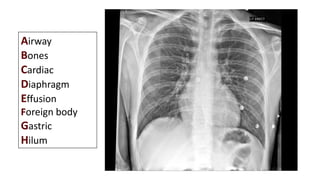

It’s All About The Anatomy!

Airway

Bones

Cardiac

Diaphragm

Effusion

Foreign body

Gastric

Hilum